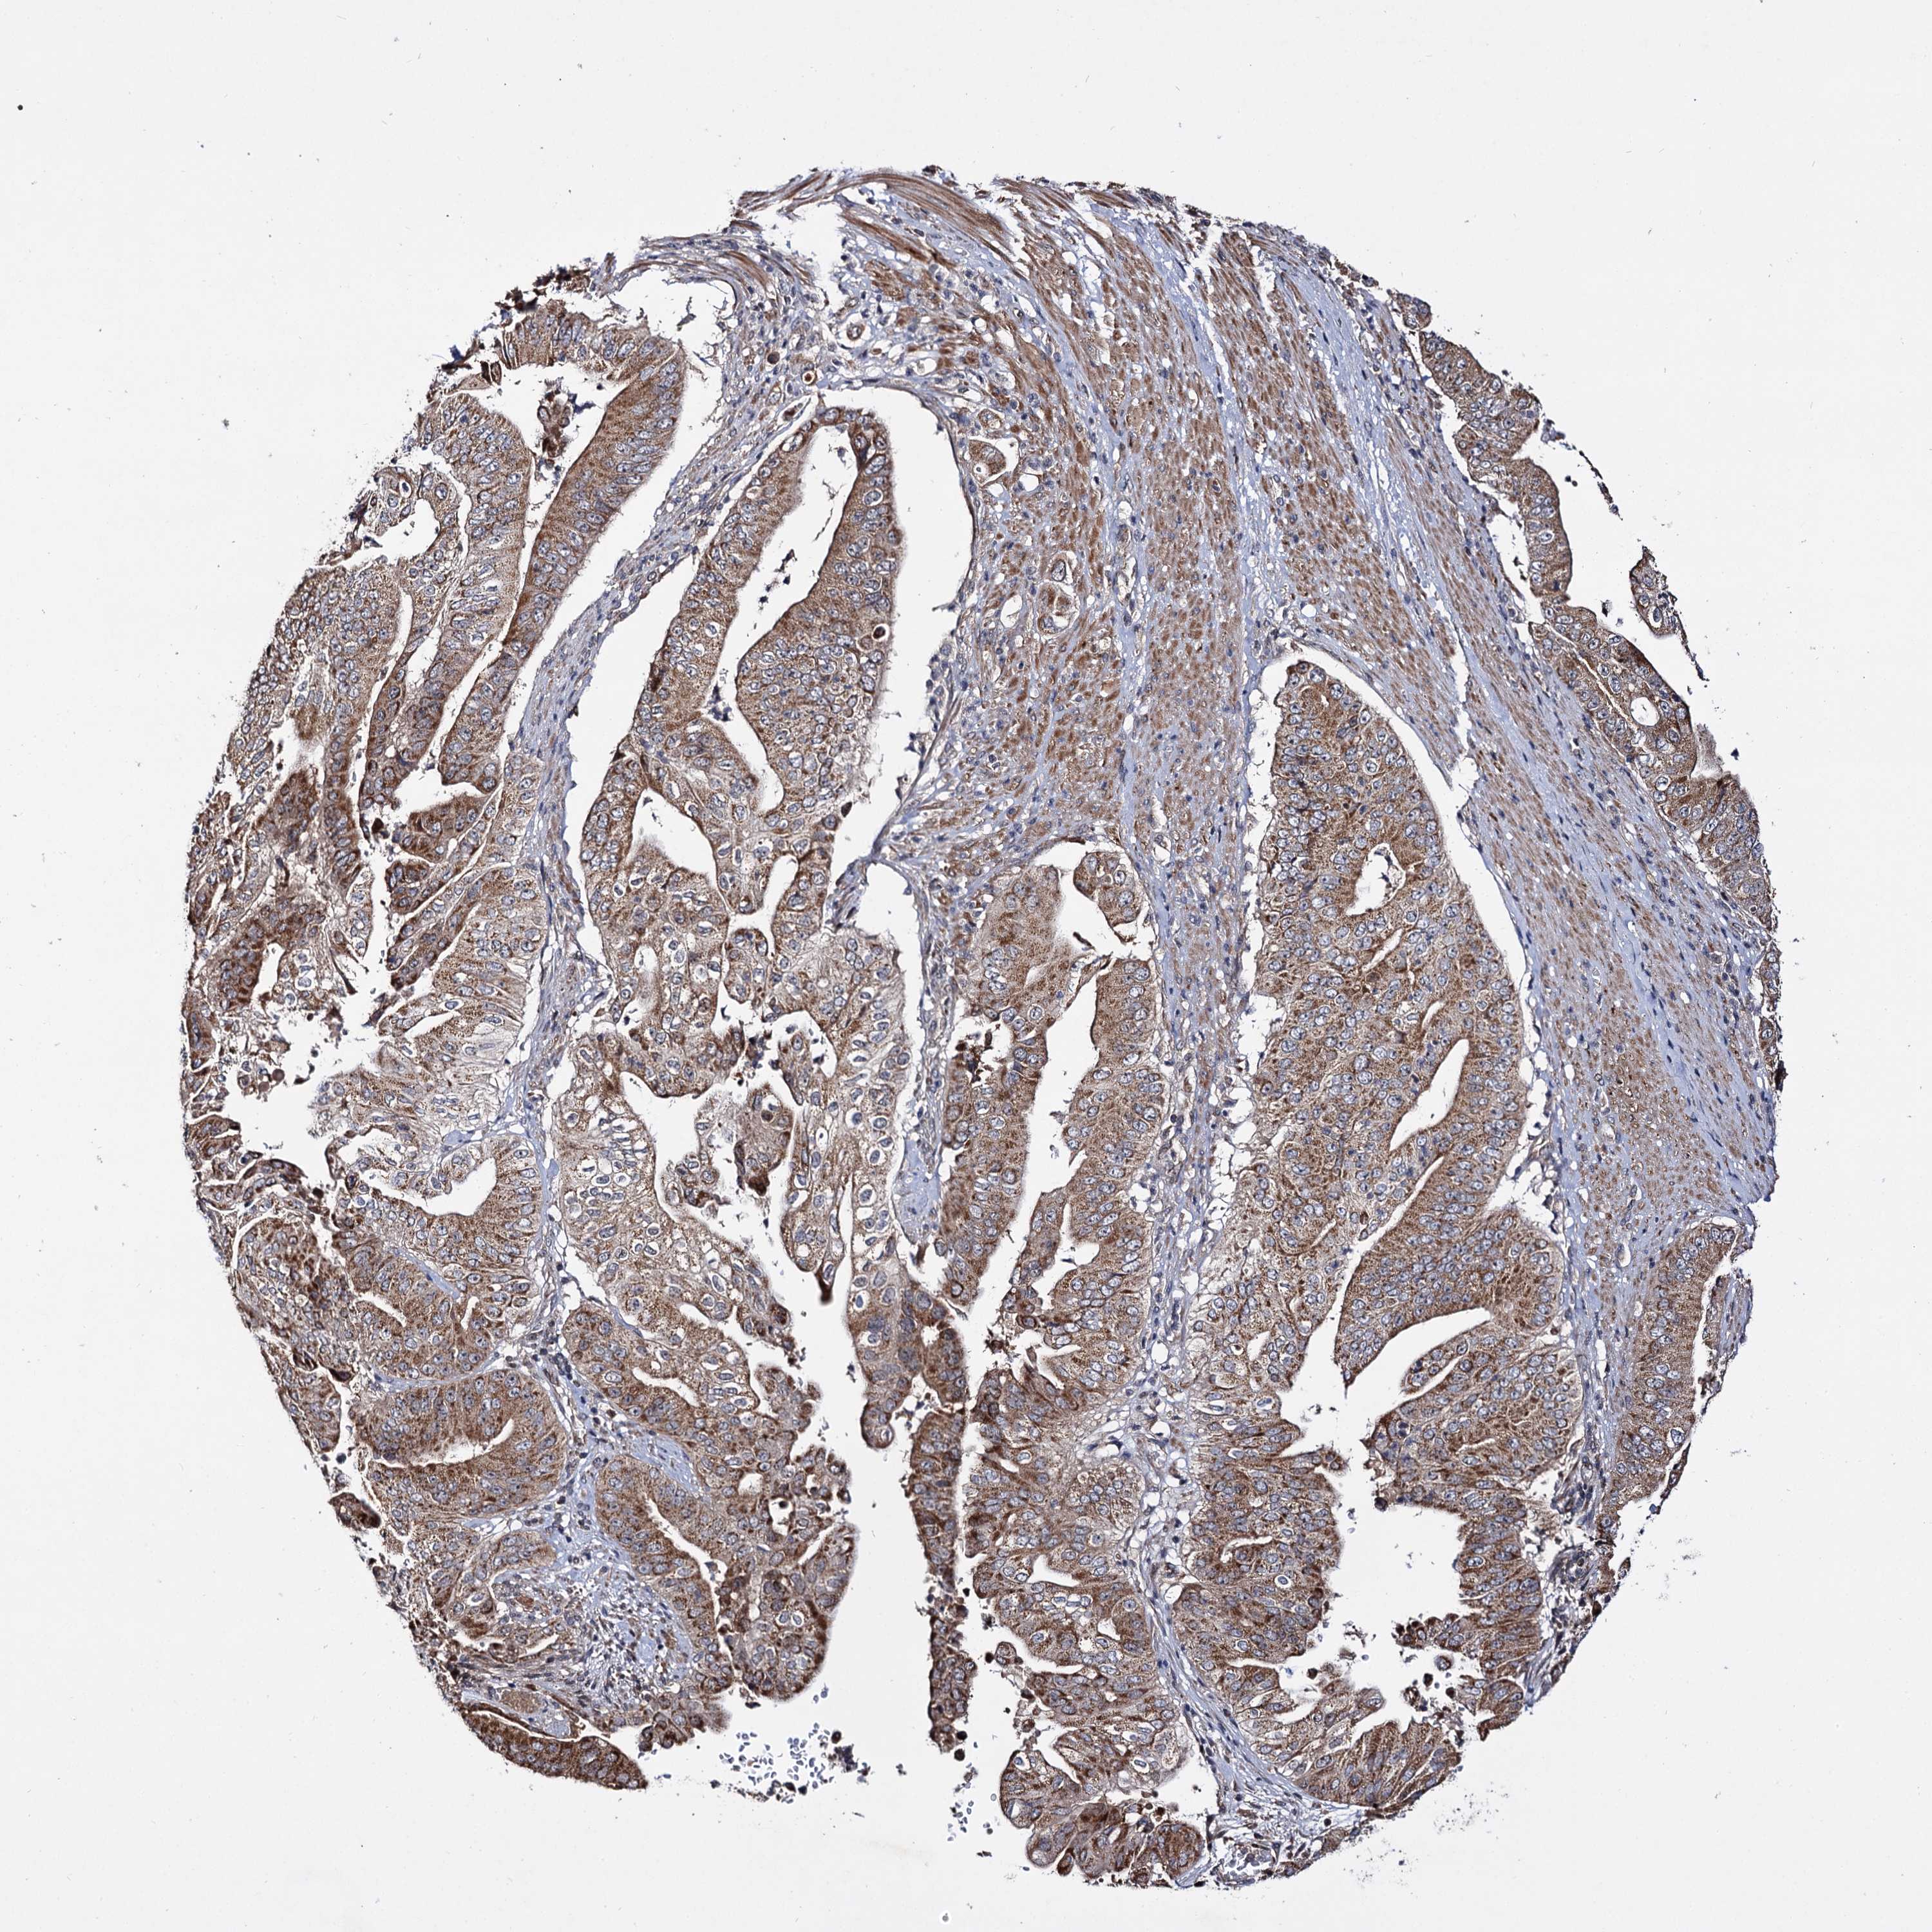

PANCREATIC CANCER - Protein expressioni

A mouse-over function shows sample information and annotation data. Click on an image to view it in a full screen mode. Samples can be filtered based on level of antibody staining by selecting one or several of the following categories: high, medium, low and not detected. The assay and annotation is described here.

Note that samples used for immunohistochemistry by the Human Protein Atlas do not correspond to samples in the TCGA dataset.

Antibody stainingi

Antibody staining in the annotated cell types in the current human tissue is reported as not detected, low, medium, or high, based on conventional immunohistochemistry profiling in selected tissues. This score is based on the combination of the staining intensity and fraction of stained cells.

Each image is clickable and will lead to virtual microscopy that enables deeper exploration of all samples and also displays staining intensity scores, fraction scores and subcellular localization as well as patient and tissue information for each sample.

Antibody HPA039395

Staining

High

Medium

Low

Not detected

Intensity

Strong

Moderate

Weak

Negative

Quantity

>75%

75%-25%

<25%

None

Location

Nuclear

Cytoplasmic/membranous

Cytoplasmic/membranous,nuclear

Adenocarcinoma, NOS